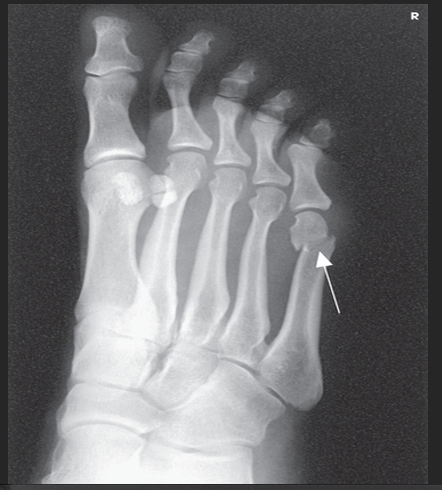

Name this projection.

AP oblique foot

Describe the position of the patient.

Seated or supine with their knee flexed and lower leg/foot rotated medially 30 degrees

Where does the CR enter?

Base of the 3rd metatarsal

What is demonstrated?

The lateral side of the foot from the toes to heel, the sinus tarsi, and the tuberosity of 5th metatarsal

The ________ metatarsals should be free of superimposition.

3rd-5th

Which metatarsals should be superimposed?

1st and 2nd

What could be done to demonstrate the opposite aspect of the foot?

Rotate the foot out laterally 30 degrees